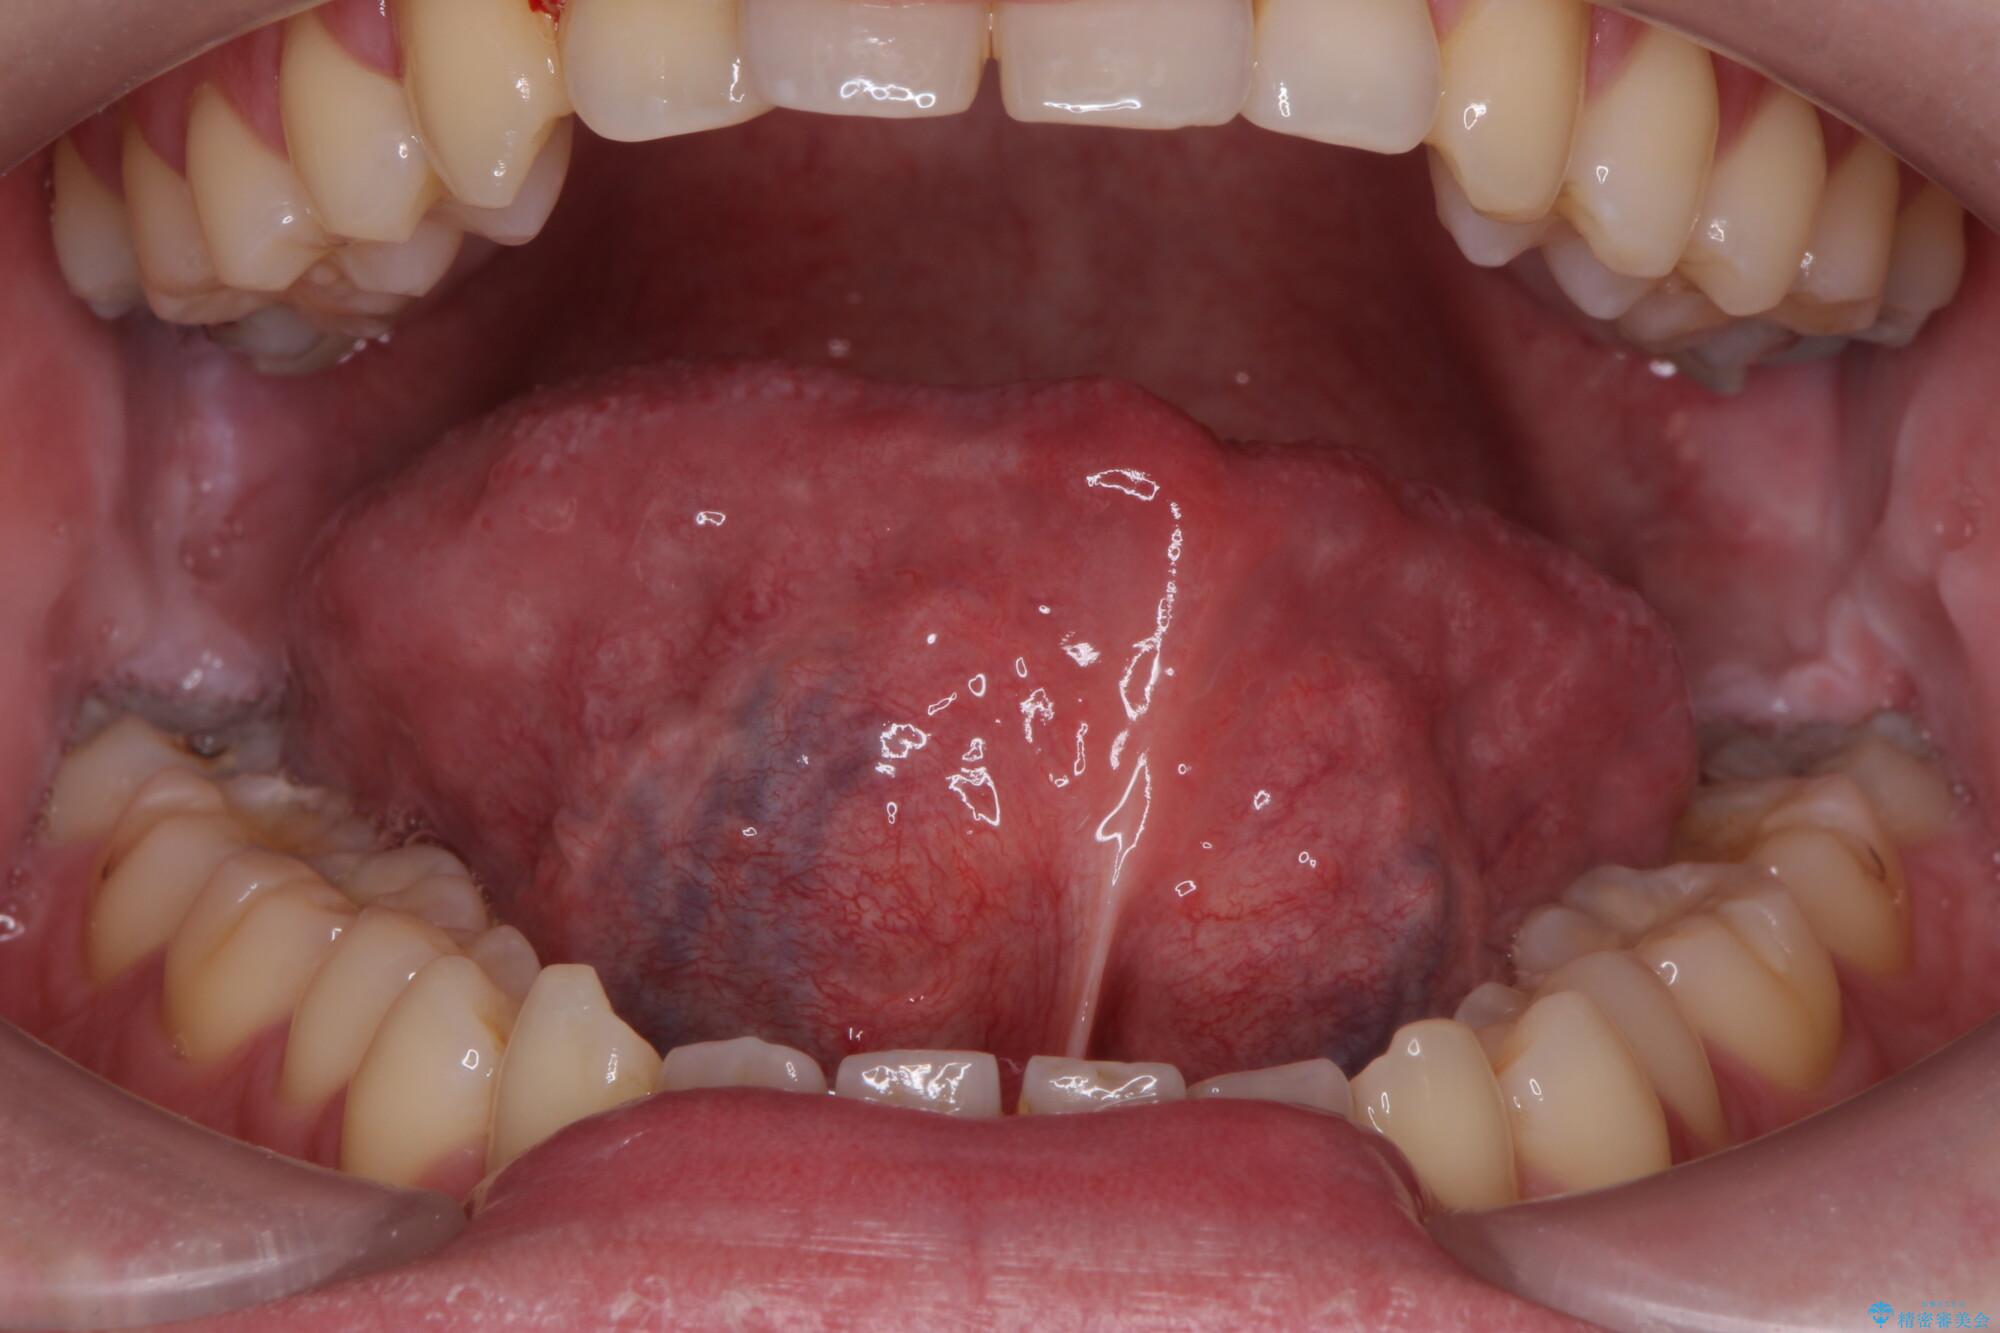

治療後

舌小帯を切除し滑舌を治したい 治療後画像 舌小帯を切除し滑舌を治したい 治療後画像

出血も少なく、舌の動きが大幅に改善しました。手術の効果を最大限に引き出し、滑舌をしっかり定着させるために、今後は舌のトレーニングも並行して行いましょう。